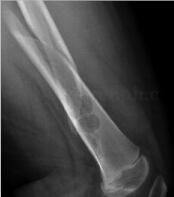

患儿9岁,男,因患儿上体育课时不慎摔伤左大腿,活动受限来院救治意外发现。近日无发热,无咳嗽,无恶心呕吐,二便正常(图1~2)。

图1 X线:左侧股骨中段断端移位,股骨中下段可见不规则透亮区,边缘可见少许硬化缘

图2 CT:股骨下段髓腔内见软组织密度影,CT值约为50HU。病变膨胀性生长,相应髓腔扩大,周围骨质受压变薄有硬化缘,髓腔内见游离碎骨及骨性分隔。病变段股骨周围软组织肿胀